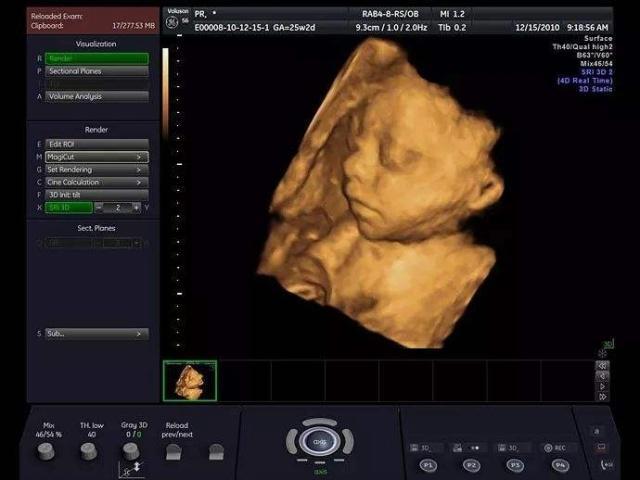

首先,你得知道,四维检查可不是随便一家医院都能做的。得找那些设备先进、技术过硬的大医院或者专业的妇产医院。比如,市中心的那些三甲医院,设备新,医生经验丰富,做四维检查那是杠杠的。

再来说说那些私立的妇产医院,虽然价格可能稍微贵那么一丢丢,但是服务态度好,环境舒适,等待时间短,对于我们这些准妈妈来说,体验感很重要嘛!

还有就是,现在很多地方都有专门的孕检中心,它们提供的四维检查服务也很不错。这些中心通常会有专门的咨询服务,你可以提前打电话问问,了解一下流程和费用,这样心里也有个底。